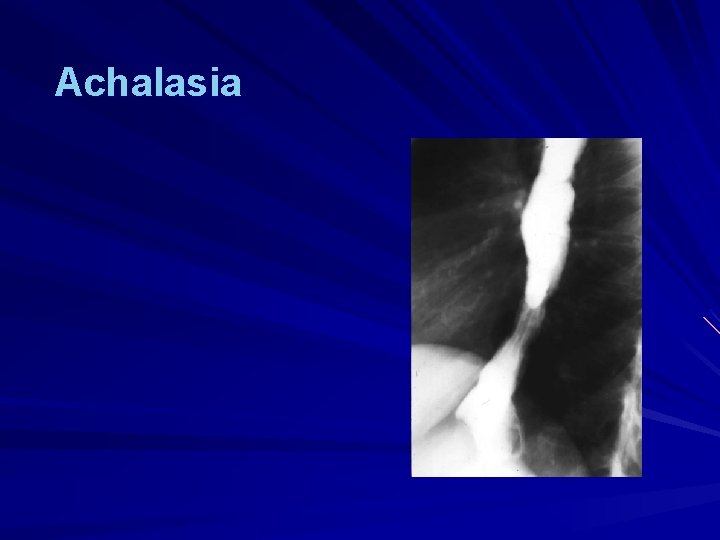

Achalasia